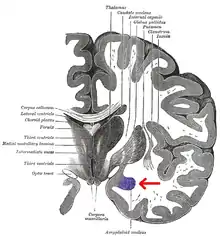

El cuerpo amigdalino, complejo amigdalino o amígdala cerebral es un conjunto de núcleos de neuronas localizadas en la profundidad de los lóbulos temporales de los vertebrados complejos, incluidos los humanos.[1] La amígdala forma parte del sistema límbico, y su papel principal es el procesamiento y almacenamiento de reacciones emocionales.[2][3]

Las regiones descritas como «amígdala» en realidad abarcan una serie de núcleos con distintos atributos funcionales llamada complejo amigdalino. Entre esos núcleos se encuentra el grupo basolateral, el núcleo centromedial y el núcleo cortical. El grupo basolateral se puede dividir a su vez en el núcleo lateral, el basal y los núcleos basales accesorios.[2][4]

El núcleo cortical está relacionado con el sentido del olfato y el procesamiento de las feromonas. Recibe información desde el bulbo olfatorio y la corteza olfatoria. El núcleo lateral, que envía proyecciones al resto del grupo basolateral y a los núcleos centromediales, recibe proyecciones desde sistemas sensoriales. Los núcleos centromediales conforman las principales sales para el grupo basolateral, y está involucrado en la activación emocional en ratas y gatos.[3][4][5]